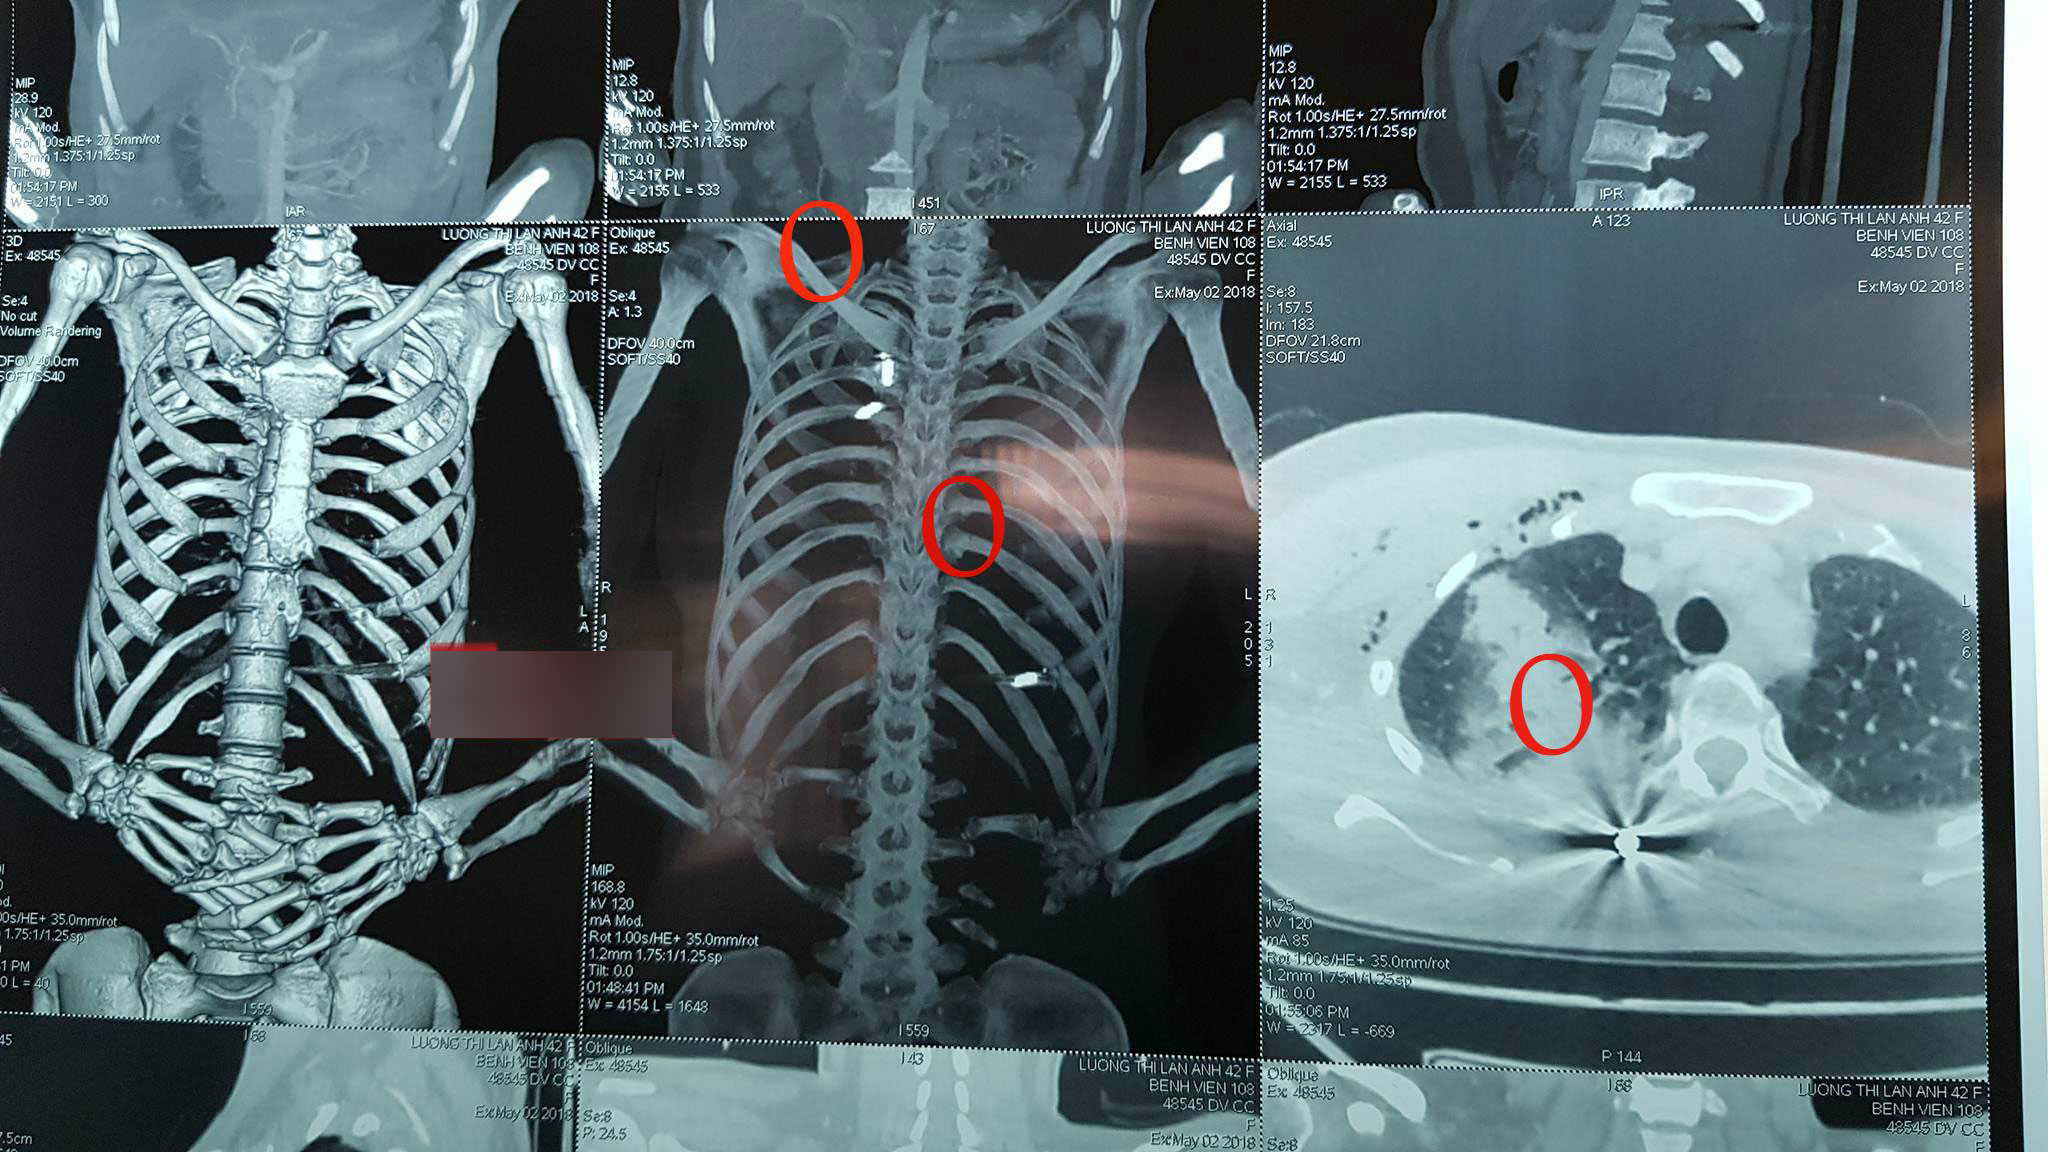

Liên quan đến tình hình sức khỏe của nạn nhân Thương Thị Lan A. (44 tuổi, trú tại TP. Bắc Giang, nữ Giám đốc công ty trạm trộn bê tông Giang Ninh), nạn nhân trong vụ nổ súng xảy ra vào ngày 2/5 tại thôn Hàm Long, xã Tiền Phong, huyện Yên Dũng, tỉnh Bắc Giang, PV đã có cuộc trao đổi với các bác sĩ của khoa Phẫu thuật lồng ngực, bệnh viện Trung ương Quân đội 108.

Bà Bùi Ngọc Huệ, điều dưỡng trưởng của khoa Phẫu thuật lồng ngực, cho biết: “Bệnh nhân A. được đưa vào đây trong tình trạng hoàn toàn tỉnh táo, có thể giao tiếp được. Nhưng trên người phía sau tai, phần cổ và trước ngực có nhiều vết thương hình tròn nhỏ do vết đạn bắn vào người. Thể hiện trên phim chụp thì cho thấy có nhiều vết đạn găm vào trong người của chị A..

Khi được đưa vào đây, nạn nhân bị tràn dịch màng phổi và chảy máu màng phổi do có một viên đạn bắn xuyên vào phổi. Hiện tại, chúng tôi đang hoàn tất các xét nghiệm để tiến hành phẫu thuật lấy viên đạn ra khỏi người chị A.”.